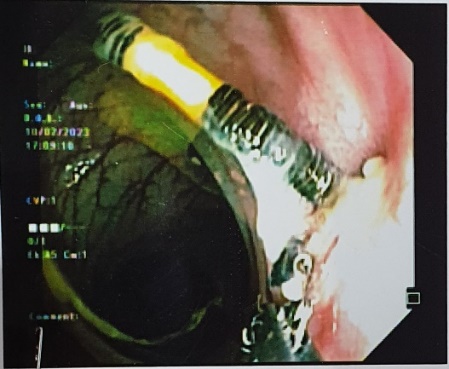

Khoa Phẫu Thuật Tiêu hóa – Gan mật tụy vừa điều trị phẫu thuật một trường hợp vòng tránh thai đâm xuyên thành tử cung vào thành đại tràng Sigma sau ba năm đặt vòng. Đó là trường hợp chị H.H.L (38 tuổi) vào viện vì đau bụng vùng chậu dưới rốn âm ỉ, kèm đi ngoài ra máu. Chị L có tiền sử đặt dụng cụ tránh thai cách 3 năm và không đi kiểm tra lại. Sau khi hỏi bệnh, thăm khám và làm các xét nghiệm cần thiết, soi đại tràng và chụp cắt lớp vi tính, cho thấy hình ảnh dụng cụ tử cung nằm 1 đầu ở trong lòng đại tràng sigma, 1 đầu nằm chặt trong thành của đại tràng sigma phía bờ mạc treo. Với vị trí này, bác sĩ không thể lấy dụng cụ tử cung qua đường nội soi ống mềm do có thể gây thủng đại tràng vào ổ bụng làm nặng thêm cho người bệnh. Vì vậy, các bác sĩ quyết định phẫu thuật để lấy dụng cụ tử cung lạc chỗ và xử lý chỗ thủng đại tràng. Phẫu thuật nội soi hoàn toàn là phương pháp được lựa chọn vì là phương pháp ít xâm lấn nhất cho người bệnh

Dụng cụ tử cung trong thành đại tràng sigma qua nội soi đại tràng và phim CLVT